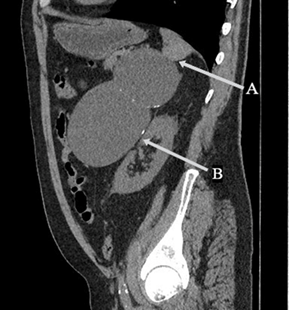

- Cystic Lymphangioma of the Pancreas: About A Case and Literature Review310.23958/ijirms/vol06-i08/1143